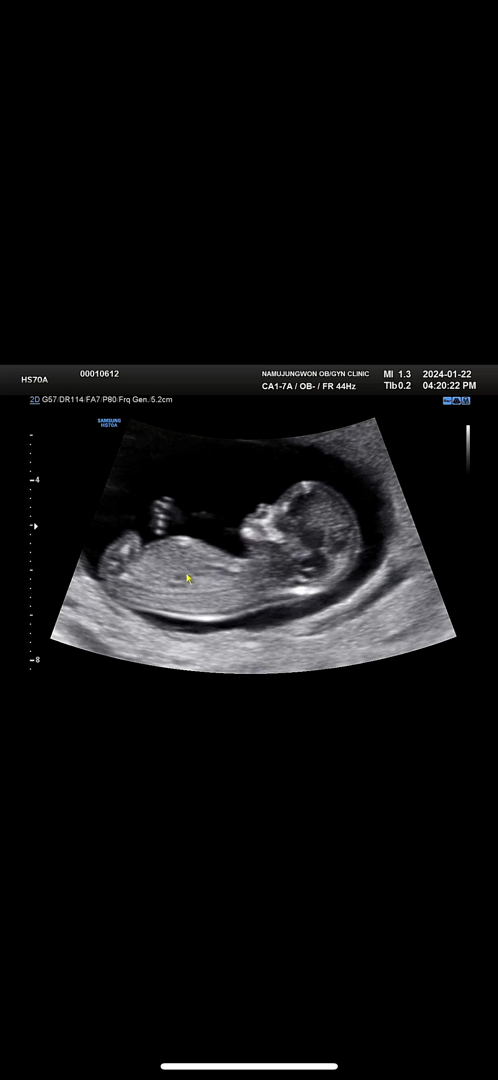

각도법이 뭐예여 11주인데

11주인데 이게 보이나용 ㅠㅠ 아들인지 딸인지 ?

12주쯤 되야 보여요 각도법은 아이척추와 다리위치로 알아보는성별이예요

아 네 감사합니당 😊 4주뒤에 오라고 했으니 그때는 확실히 보이겠네용